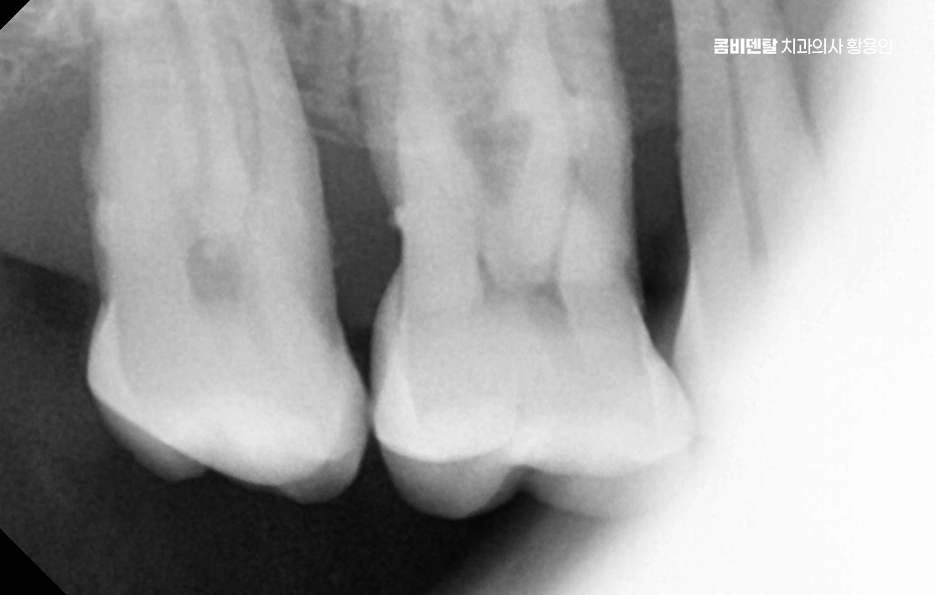

어금니 발치후 임플란트 안하면 먼저 생기는 문제는 치아 이동 현상으로 사람의 치아는 서로 의지하면서 균형을 맞추고 있는데, 어금니 하나가 빠지게 되면 그 자리를 메꾸기 위해 옆 치아들이 점점 쓰러지듯이 기울어지며 또 위아래 맞물리던 치아는 상대 치아가 사라지면 아래로 내려오거나 위로 솟구치면서 위치가 틀어질 수 있어요

결국 전체 치열이 뒤틀리고 교합이 망가지게 되는 것인데 이건 단순한 배열 문제가 아니라, 턱관절까지 영향을 줄 수 있는 변화로 이어지는 거예요.

그리고 사실 골 흡수의 문제가 무척이나 큰데 즉 잇몸뼈가 점점 사라지는 현상으로 치아가 뿌리로 잇몸뼈에 자극을 주고 있어야 뼈가 유지되는데, 치아가 빠진 상태로 계속 방치되면 그 부위 뼈는 서서히 꺼지듯이 흡수되기 시작하는 거예요.

나에게 맞는 치료를 하기 위해서는 정확한 진단과 설계가 중요하며 CT 촬영 등을 통해 신경 위치, 뼈의 양, 두께 등을 정밀하게 진단한 다음, 교합과 치열 구조에 맞는 위치에 임플란트를 심는 게 중요한데 잘못된 위치에 심어지면 오래 쓰기 어렵고, 나중에 통증이나 염증이 생길 수 있었어요.